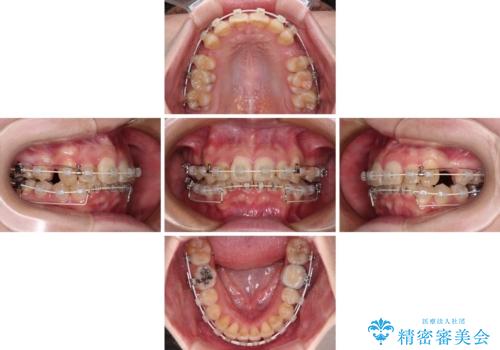

- 矯正装置

- 審美装置

- 治療期間

- 3年1ヶ月

- 治療回数

- 30回以上

上顎左右第一小臼歯の2本を抜歯し、ワイヤー装置を使用して咬み合わせ高さを改善しながら、歯列を整えて行くこととしました。